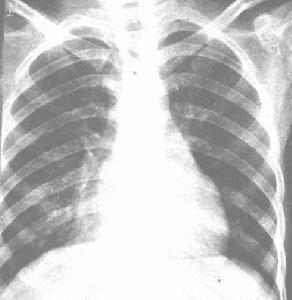

輕症:多見學齡前期及學齡期兒童早期有結膜炎,咽炎及皮疹等腺病毒感染的症狀熱程短,持續7~14天,中毒症狀輕,一般無心腦等合併症。肺部體徵與X線 與一般支氣管肺炎近似病程10~14天高熱驟降,一般症狀隨著很快好轉肺部陰影2 ~4周才能完全消失

1.呼吸道症狀多數患兒自起病時即有頻繁咳嗽,呼吸道分泌物黏稠不易咳出, 4~6天以後逐漸出現喘憋發紺、鼻扇、三凹征、梗阻性呼吸困難或呼吸衰竭。肺 部物理征出現較晚是腺病毒性肺炎的特點。發病早期呼吸音粗發熱4~5天后方可 出現肺部體徵叩呈濁音呼吸音減低或乾囉音肺實變時可聞管狀呼吸音以後漸可聞 及濕囉音或捻發音,且日漸增多,並有肺氣腫徵象。部分重症病例第2周合併胸膜反應或少量胸腔積液,胸腔積液可分離出腺病毒。